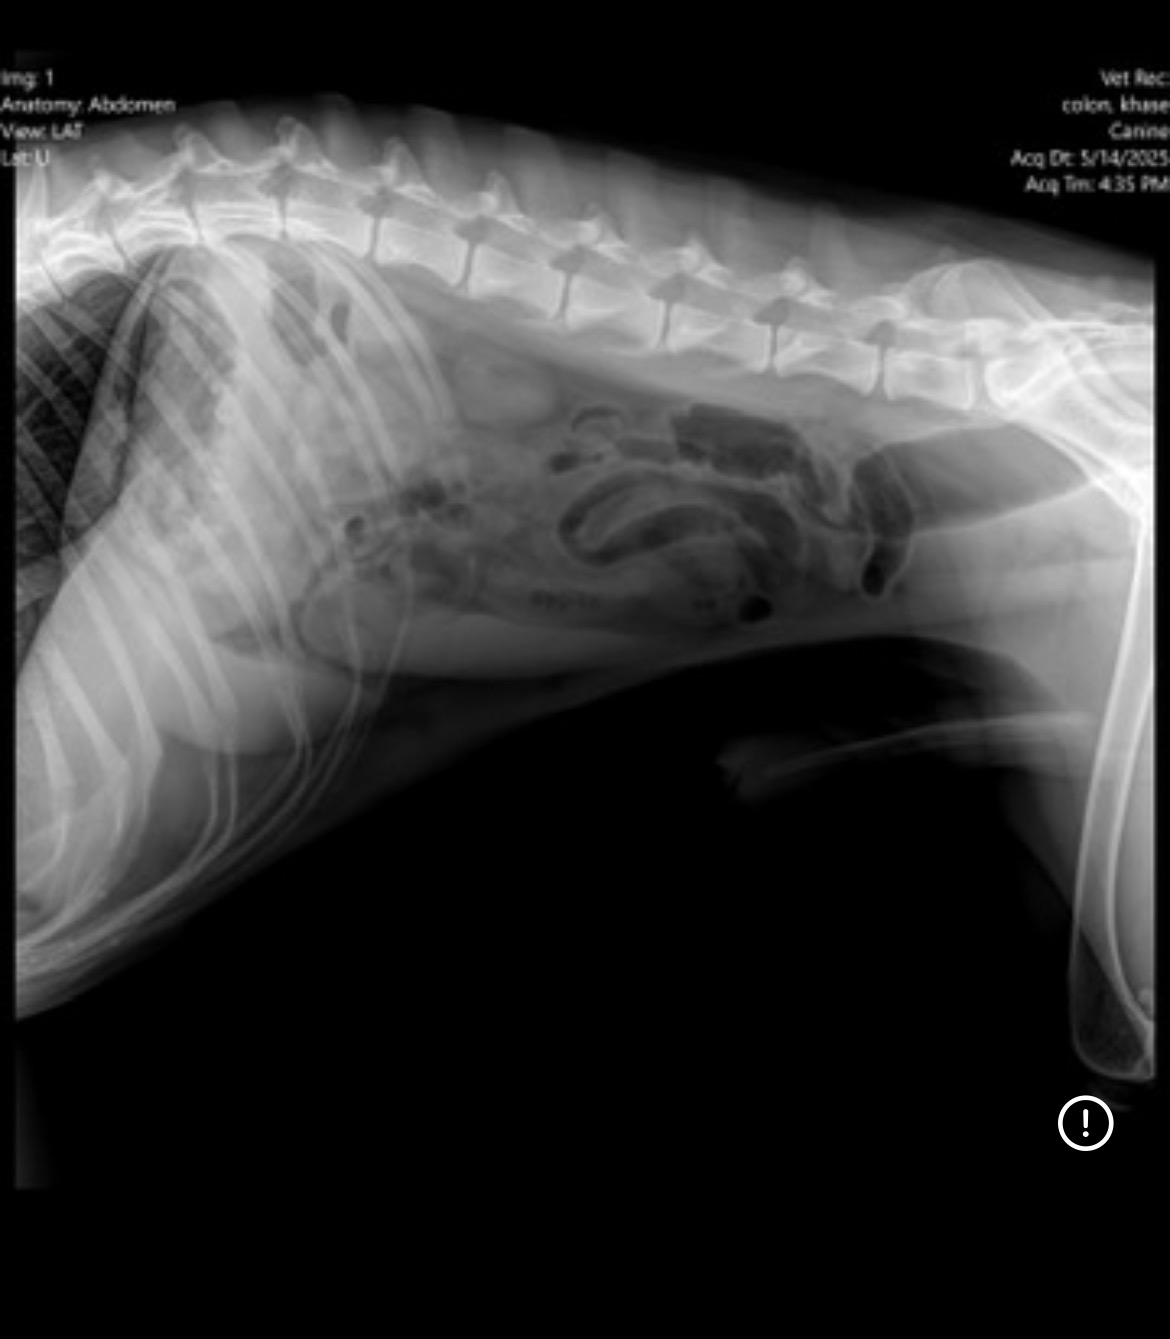

I’m reaching out with a heavy heart and a desperate plea. My dog Chase—my sweet, goofy, loyal baby—got sick Tuesday night and has rapidly declined. After rushing him to the vet, I learned he has a bowel obstruction and hasn’t been able to eat for over three days. He’s weak, in pain, and fading before my eyes.

Chase is more than just a pet—he’s my shadow, my emotional support, my family. We’ve been through everything together, and I refuse to give up on him now. But the cost of saving his life is more than I can manage alone. His treatment, including scans, surgery, and aftercare, is expected to total $9,000.